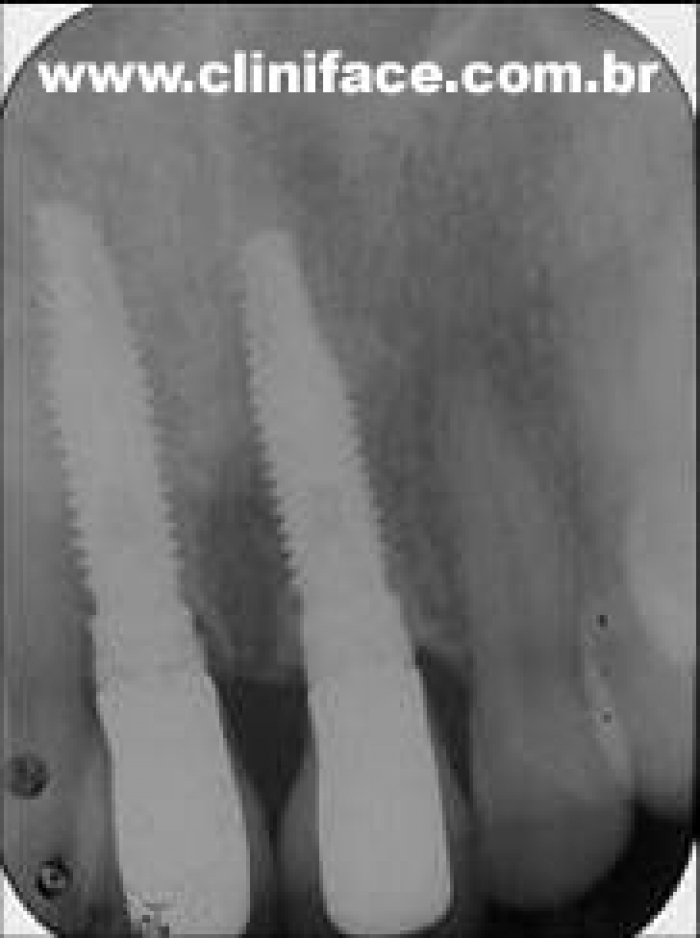

Raio X final